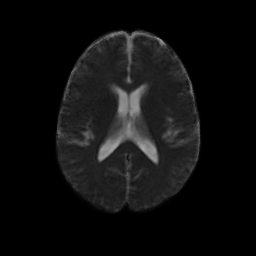

An initial test was performed by using the procedure on a set of images of healthy subject at age one year. The results of the tensor averaging are shown on the right. Tractography was also performed on the mean atlas image as shown.